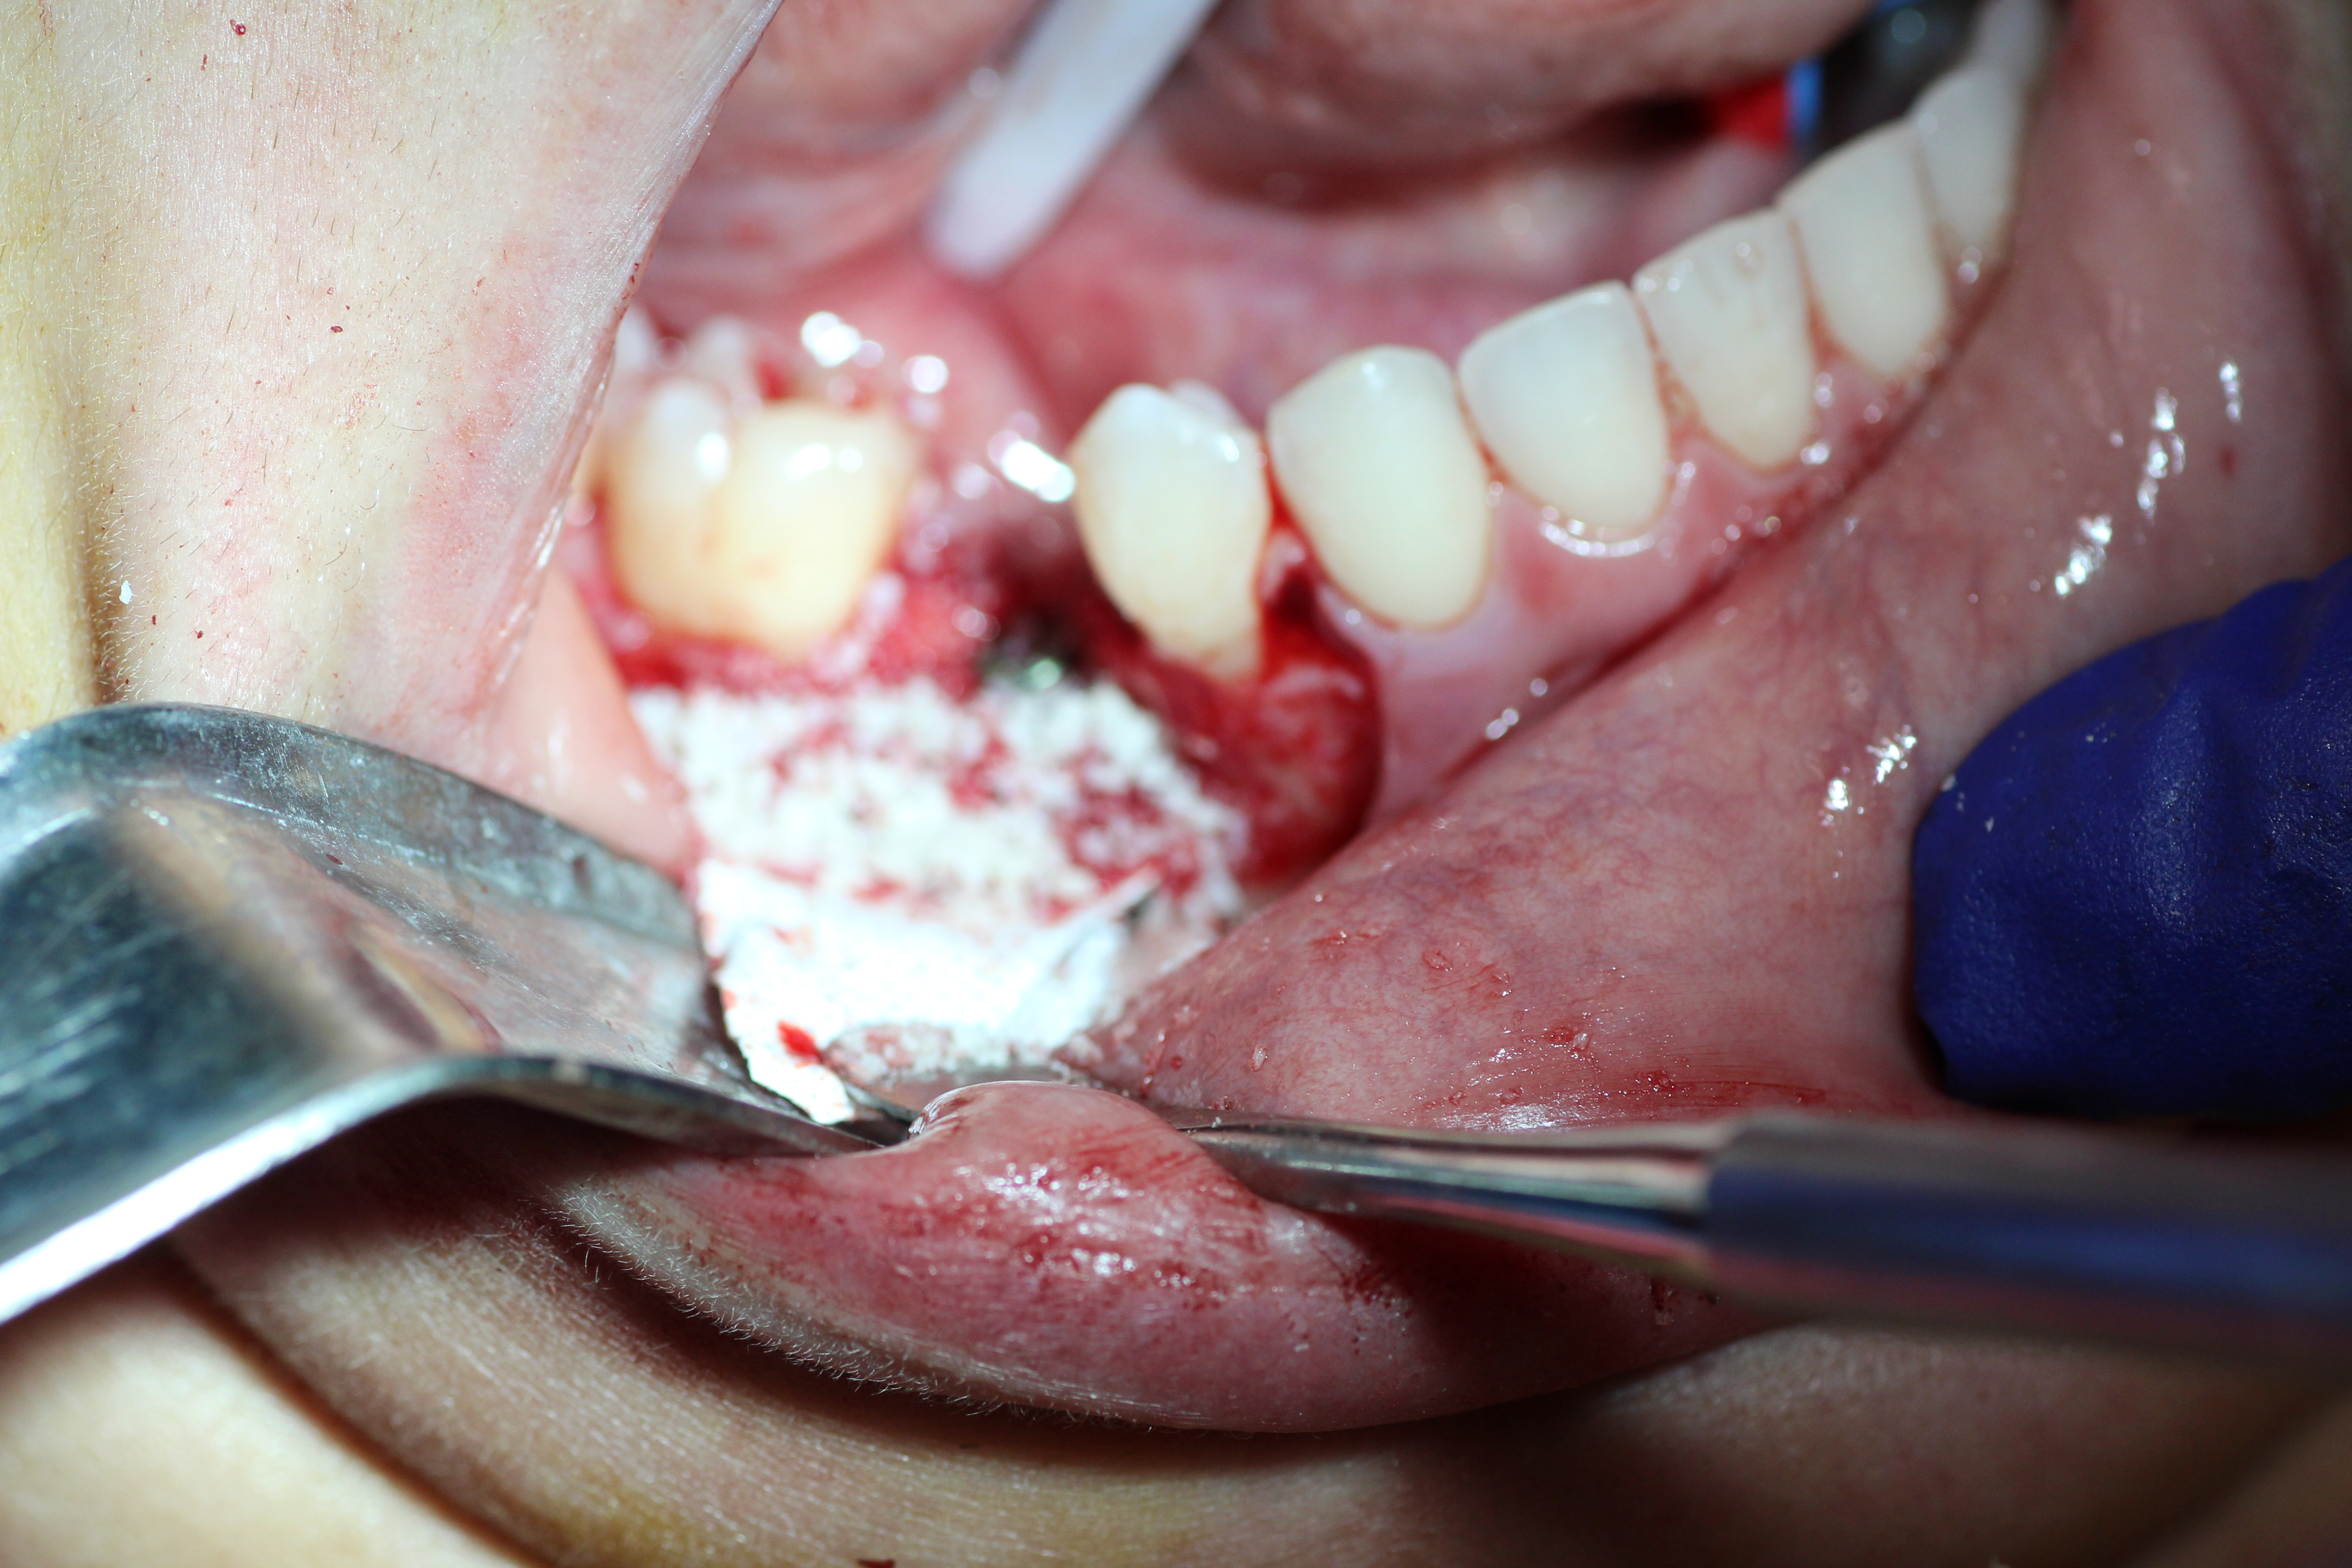

Immediate placement with bone guided regeneration.

- Implant in place with mental nerve isolated.

- Buccal plate decorticated.

- Bone graft in place.